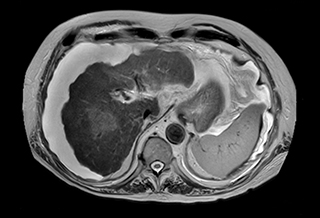

Free breathing abdominal MRI with VitalEye

Ascites can be hard to image, but excellent result is obtained with Ingenia Ambition. This high resolution image demonstrates the high quality that can be obtained with VitalEye and the patient just breathing normally. The acquisition time is fast thanks to the accuracy of the respiratory gating with VitalEye** and it also saves the time needed to put a respiratory belt on the patient.

3D T2 with VitalEye

3D T2 with VitalEye